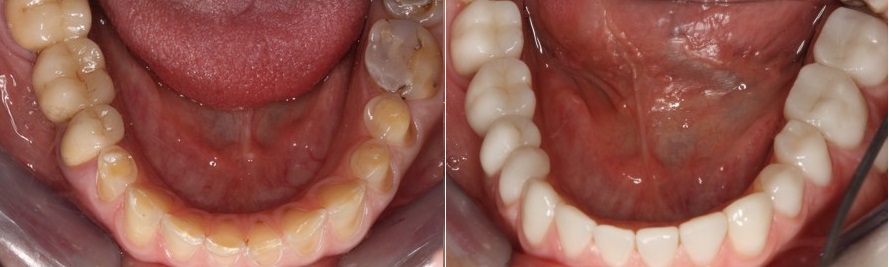

Αφού αποκατασταθούν τα πρόσθια δόντια, αρχίζει η σταδιακή αλλαγή των προσωρινών αποκαταστάσεων των οπίσθιων δοντιών. Τα προσωρινά σφραγίσματα αφαιρέθηκαν ανά τεταρτημόριο και αντικαταστάθηκαν με επένθετα πορσελάνης.

Στην φωτογραφία που ακολουθεί βλέπουμε την εικόνα των δοντιών της ασθενούς πριν και μετά την συγκόλληση των όψεων ρητίνης και πορσελάνης στα πρόσθια δόντια και των επένθετων πορσελάνης στα οπίσθια δόντια της άνω γνάθου.

Η εικόνα των δοντιών της κάτω γνάθου πριν και μετά την αποκατάσταση